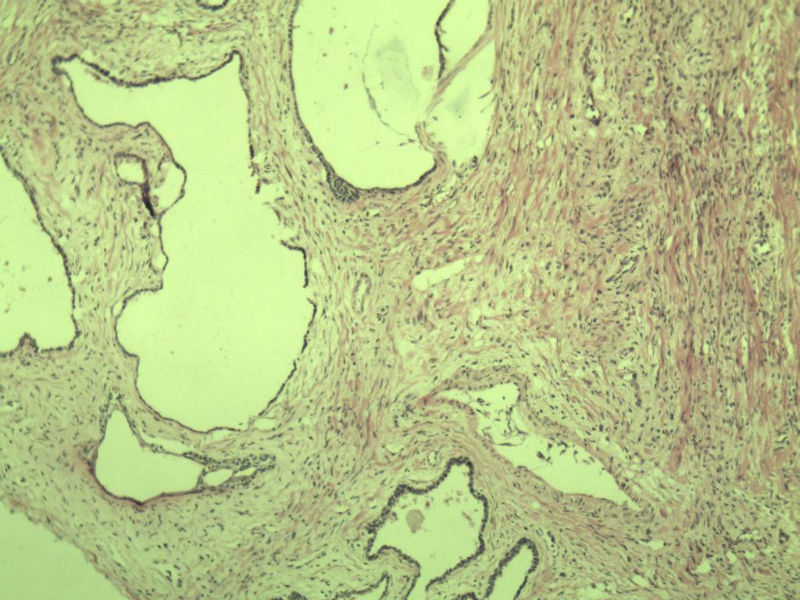

男 75岁 因排尿困难半年行前列腺切除术,体积 4 × 3 × 2.5 cm3,切面灰白,实性,质韧。请各位老师看看 有问题没? 谢谢了!

高级别上皮内瘤变,建议免疫组化:P63、34BE12、P504S

前列腺增生症伴鳞化

良性前列腺增生伴尿路上皮化生

前列腺增生伴尿路上皮鳞化及Brown巢形成,未见恶性。